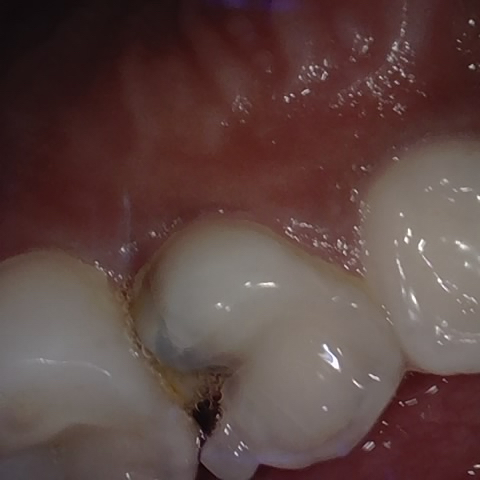

Image 153 / 1103

NHD39174

Annotated as "Good"

Original Image Rendering Image